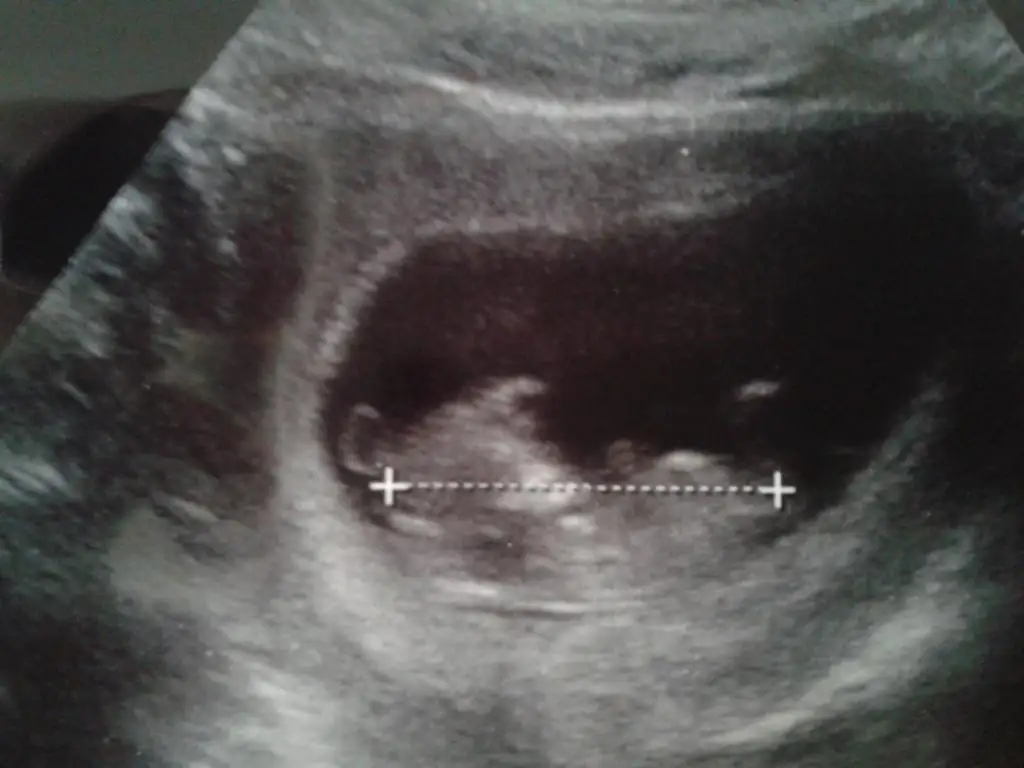

bunlar da bebişimin son fotoları teyzeleri allahıma bın sukur hala benımle bebegım bırakmadı annecıgını maasallah kuzumaaaa :nazar::nazar::nazar:

Eki Görüntüle 495487

Eki Görüntüle 495488